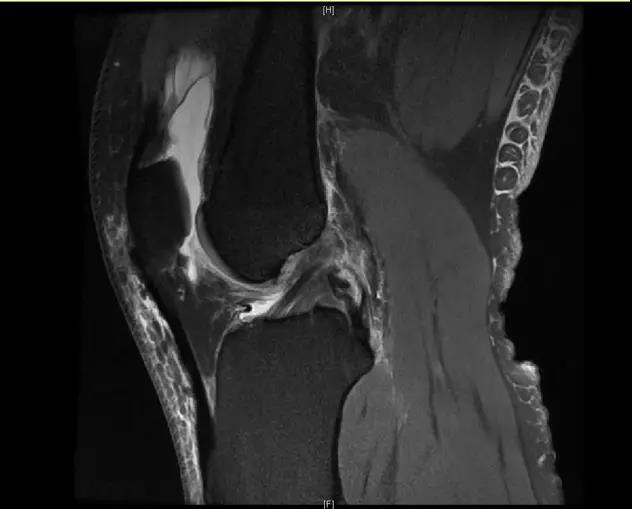

【朗润影像档案】磁共振影像病例分享(编号20180330)

【朗润影像档案】20180330磁共振影像病例结果讨论